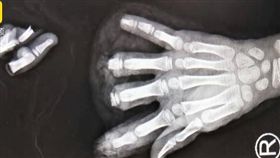

驚!6歲男童在校中指遭門夾斷急送醫

新北市汐止區某國小內,今天(13日)中午12時許,1...

出教室遇強風門突關上指遭夾斷…校方回應

新北市汐止區某國小一名小一男童,昨(13)日中午12...